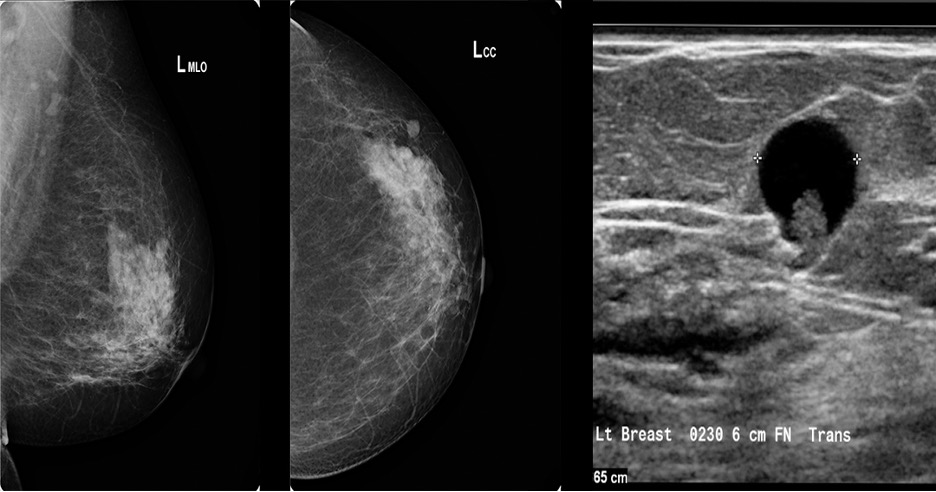

- Ultrasound

- Simple

- Anechoic throughout with posterior acoustic enhancement

- Complicated

- Homogenous low-level internal echoes with debris, thick walls, or thick septa

- No solid components

- Complex

- Fluid and solid components without posterior wall enhancements

- Well-defined solid mass with isoechogenicity

- Often found on routine mammography, but ultrasound is recommended if there is a palpable mass

- Will show a mass within a cystic space